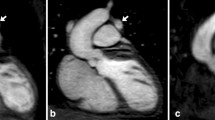

All patients had undergone CMR under deep sedation (propofol anesthesia). The mean total scan time was 4:22 ± 1:44 min for REACT CMRA and 1:51 ± 0:18 min for contrast-enhanced steady-state CMRA (P < 0.001). A representative imaging example of both CMRA methods is shown in Fig. 2.

A 7-year-old boy with congenital aortic valve dysplasia (non-reformatted water-images in coronal view). The example demonstrates comparable image quality between native relaxation-enhanced angiography without contrast (REACT) and contrast-enhanced cardiovascular magnetic resonance angiography (CMRA) with excellent fat suppression, high contrast and good vessel border delineation. The left coronary origin is clearly delineated. The left atrial appendage lateral to the main pulmonary artery is partially covered. Note the aortic regurgitant jet due to diastolic acquisition